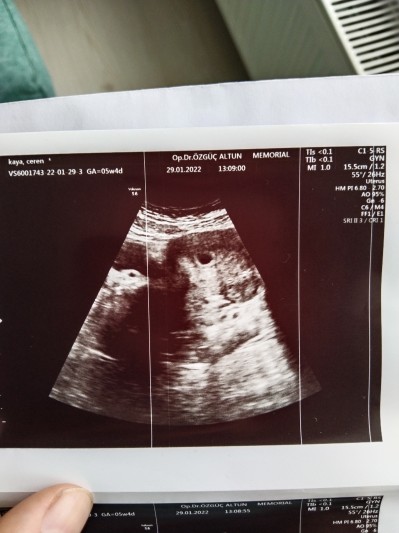

Merhaba anne adayları 5+6 hamileyim ayın 29 şunda dok. Gittik çok şükür kese gözüktü haftaya ayın 7 sinde gel kalp atışını duyalım dedi sizce duyulurmu bide kese boyutu nasıl dün beta HCG verdim 6227

Gebelik haftası 5